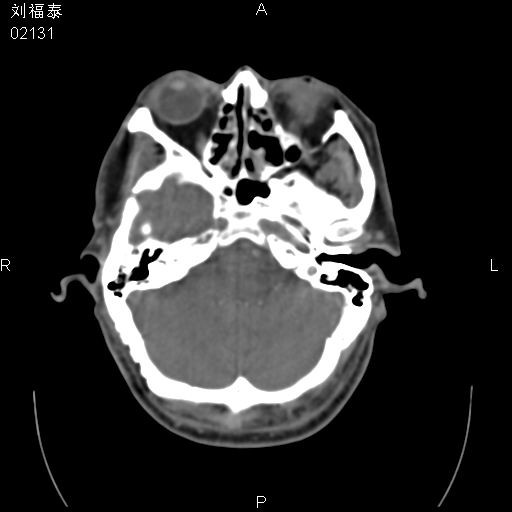

以下是引用余辉在2008-3-4 14:00:00的发言:[br]考虑左眼球黑色素瘤或血管源性肿瘤可能性大,建议增强检查

以下是引用余辉在2008-3-4 14:00:00的发言:[br]考虑眼球黑色素瘤或血管源性肿瘤可能性大,建议增强检查

以下是引用zsl6918在2008-3-4 15:08:00的发言:[br]现有征象只能提示球内出血,视网膜脱落,至于是否为肿瘤性病变需mri检查。